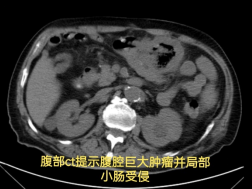

胃肠·甲状腺外科罗昭锋副主任医师会诊后,结合患者手术史与影像学检查,作出关键判断:结肠肿瘤复发并活动性出血——此时,可能只有外科手术才能扭转乾坤。

经积极输血、肠镜证实诊断后,患者转入胃肠·甲状腺外科接受手术治疗。术中探查到如同"炸弹"一样的巨大肿瘤。经仔细"拆弹",团队完整切除了出血部位的复发肿瘤,以及被侵犯的 3 处小肠。